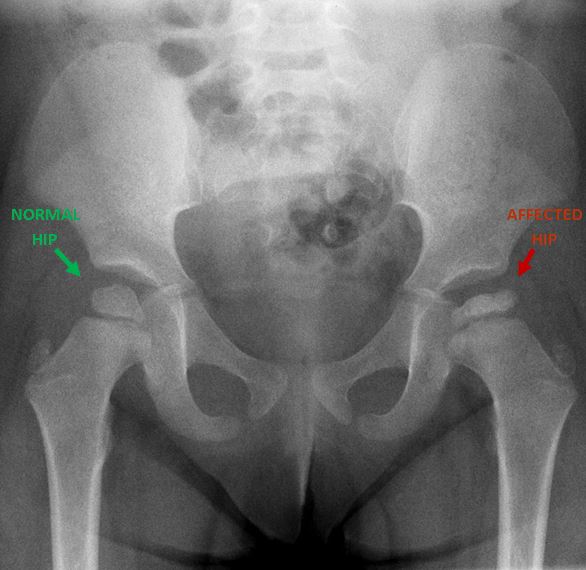

You may be thinking why we are worried about a disease which is self limiting and not life threatening! By the time Perthes comes and goes, it damages the structure of bone (this process is called avascular necrosis) resulting in loss of shape of the ball. This abnormal shape persists throughout life and may even worsen. It is easy to understand that any change in smooth shape of the joint can lead to early wear and tear (osteoarthritis hip) of it. This results in a painful joint in the prime age of the person (40s), which limits his activities and is usually treated with a major total hip replacement surgery.

After discussing your child’s symptoms and medical history, your doctor will conduct a thorough physical examination and take x rays of the hip. Usually 1-2 x rays are adequate to make the diagnosis of Perthes disease, but sometimes confirmation diagnosis or treatment planning may need MRI scan of hips.

A child with Perthes can expect to have several x-rays taken periodically over the course of treatment. As the condition progresses, x-rays often look worse before gradual improvement is seen.

The goal of treatment is to relieve painful symptoms, protect the shape of the femoral head, and restore normal hip movement. If left untreated, the femoral head can deform and not fit well within the acetabulum, which can lead to further hip problems in adulthood, such as early onset of arthritis.